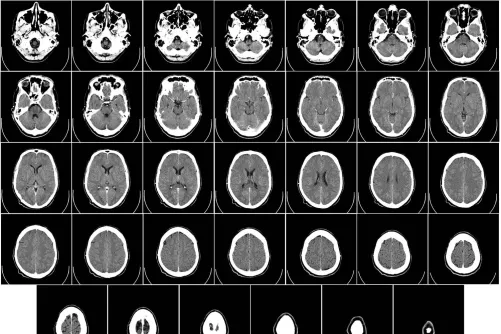

Az Európai Stroke Társaság (ESO) legmagasabb, gyémánt szintű elismerését nyerte el a Semmelweis Egyetem Idegsebészeti és Neurointervenciós Klinika stroke-ellátó programja – közölte az intézmény az MTI...